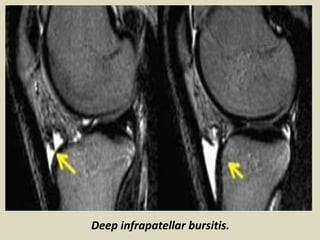

Deep Infrapatellar Bursitis

On MRI, deep infrapatellar bursitis appears as a triangular fluid collection posterior to

the patellar tendon. When found in adolescents, it should be differentiated from

Osgood–Schlatter disease. Osgood–Schlatter disease is associated with thickening and

hyperintense signal intensity of the patellar tendon, but these findings are absent in

deep infrapatellar bursitis. In addition, cases of Osgood–Schlatter disease, on clinical

examination, display pain and tenderness at the insertion of the patellar tendon.

Sagittal magnetic resonance T2 gradient showing deep infrapatellar bursal fluid.

Deep infrapatellar bursitis.